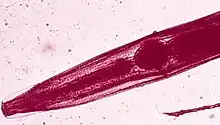

head of a pinworm

(Enterobus sp.)

(Enterobus sp.)